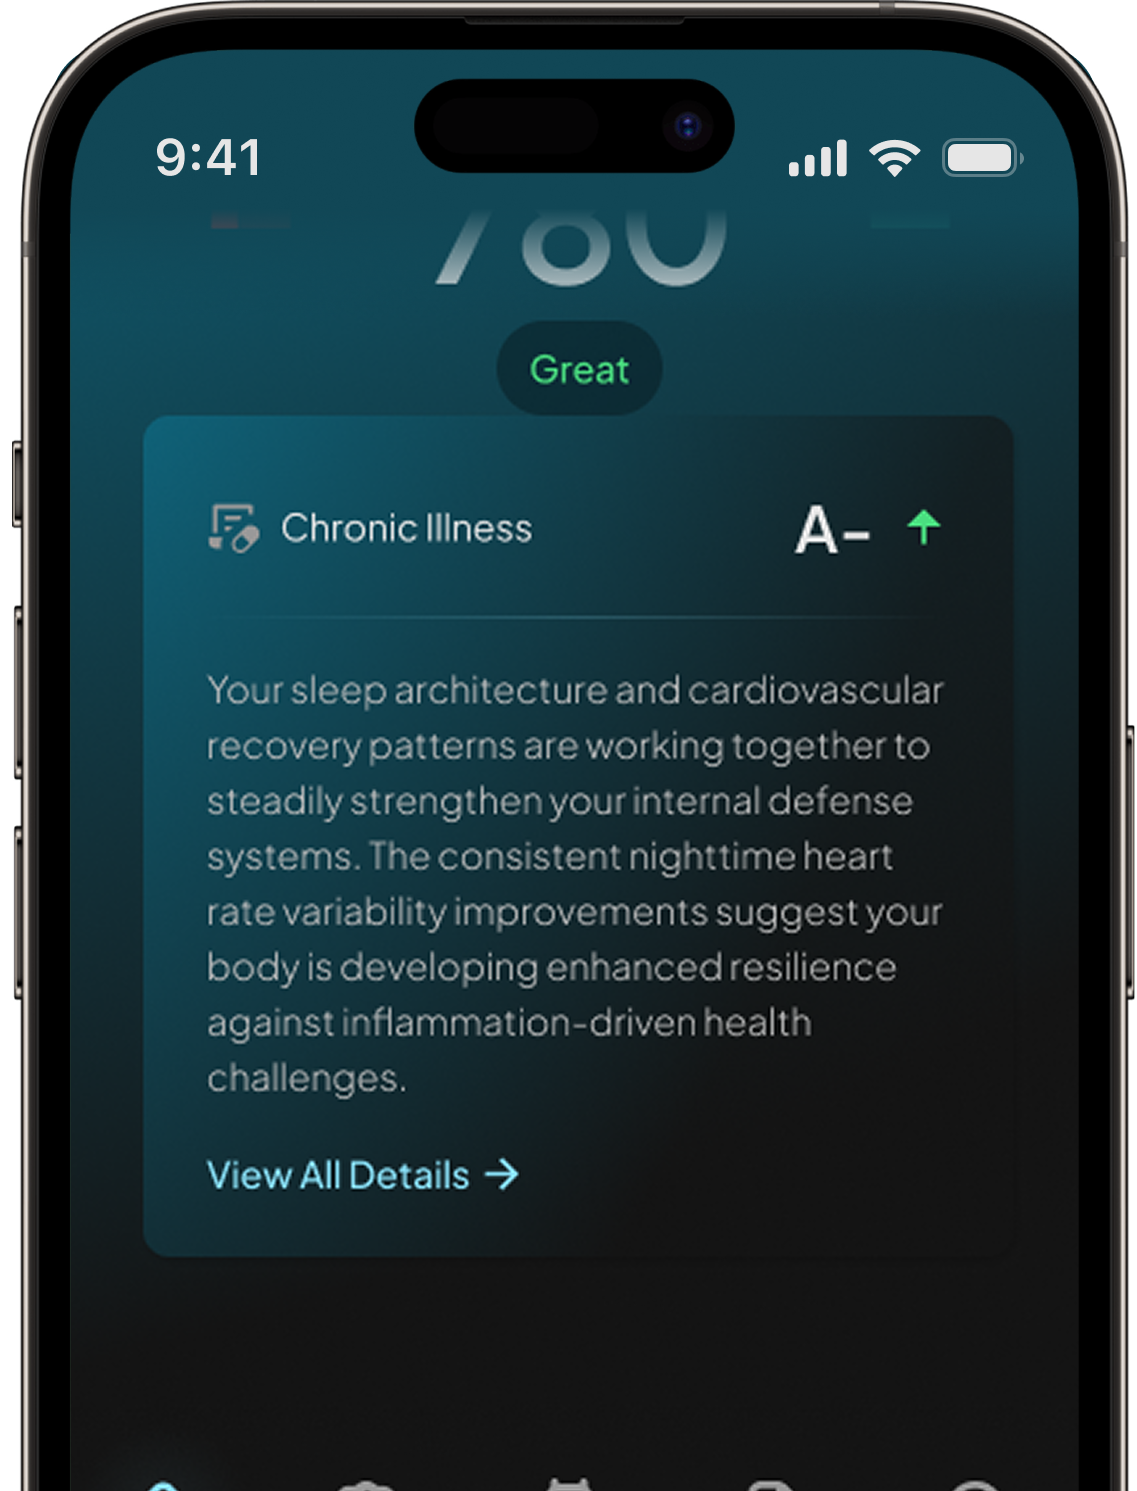

Chronic illness detection

May indicate the

onset of an illness

Identify potential health issues early and take action before they become serious.

By analyzing your body’s signals, Hume Band may detect early signs of illness—helping you take action before small issues become big problems

By analyzing your body’s signals, Hume Band may detect early signs of illness—helping you take action before small issues become big problems

We constantly scan your biometrics to detect early signs of stress, immune decline, inflammation, and recovery delays—so you can act before illness takes hold.